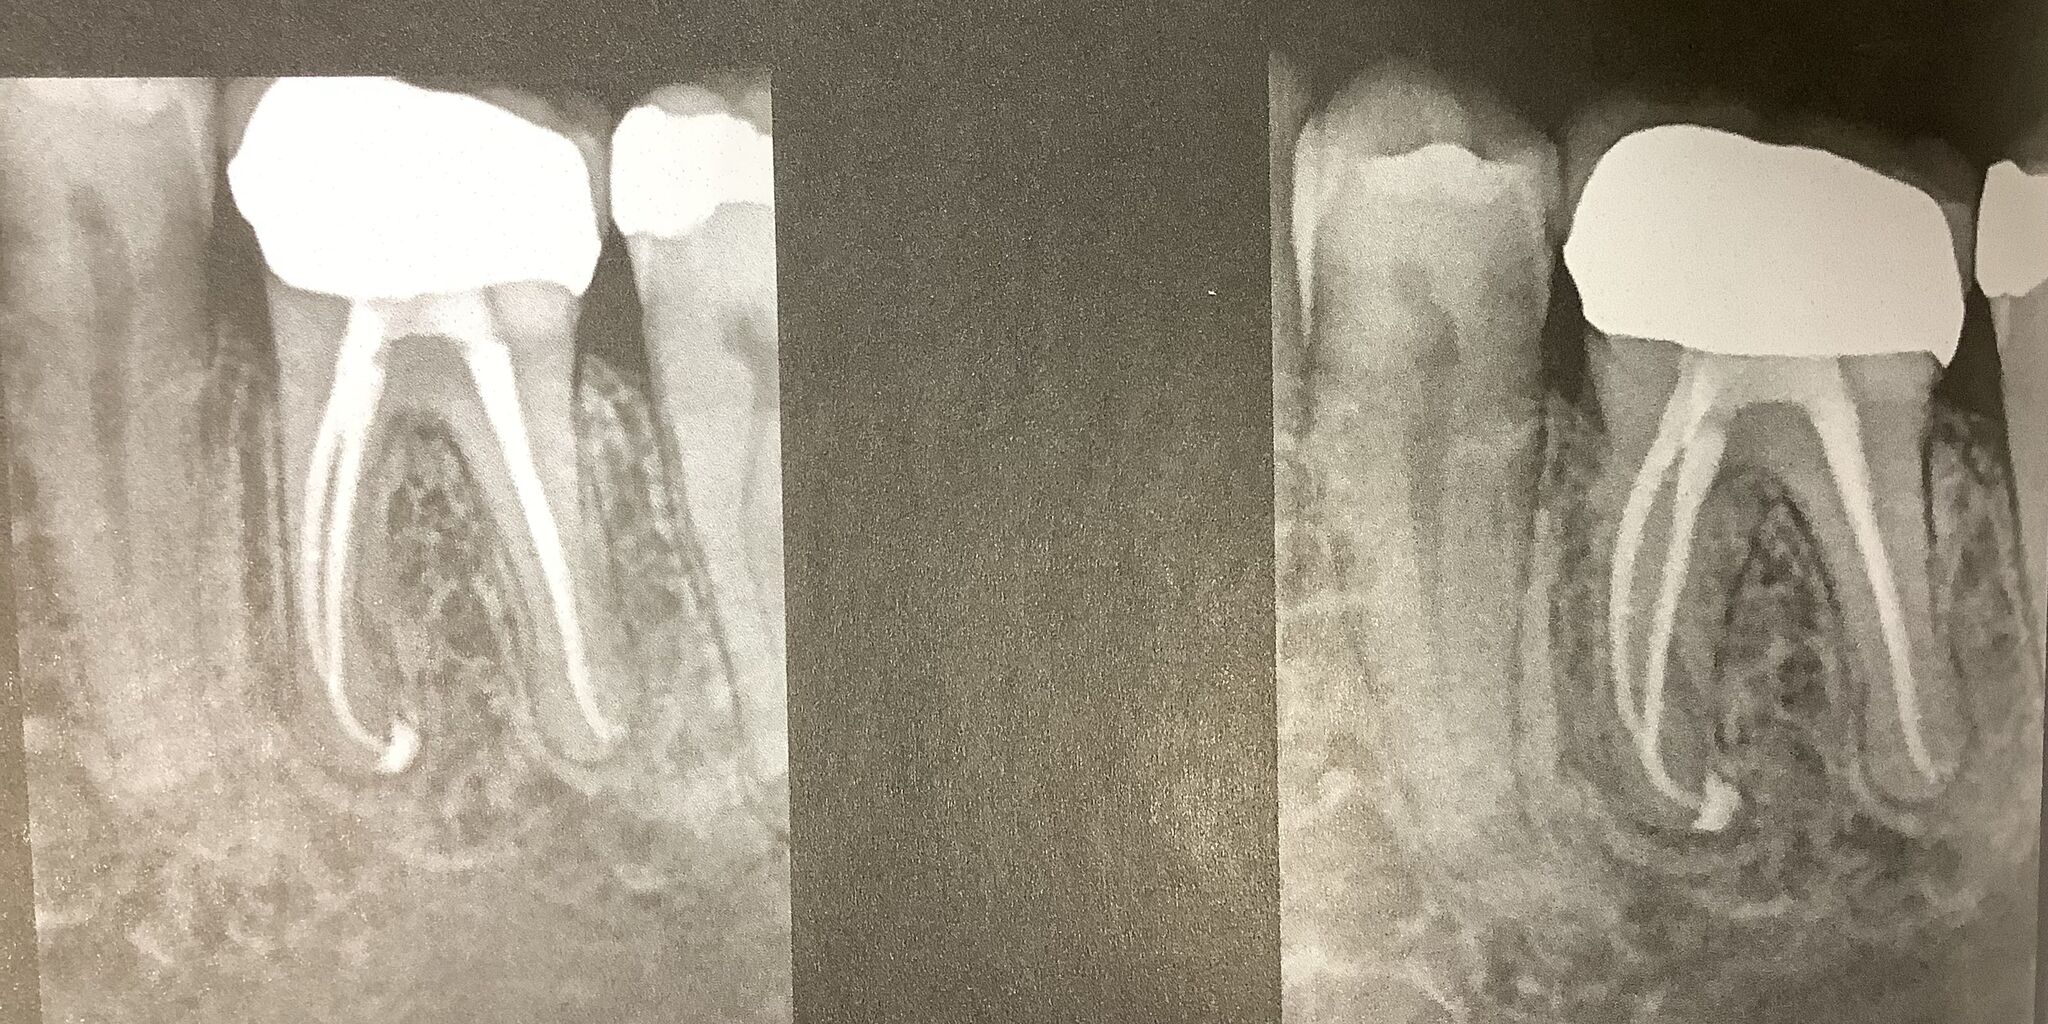

3年後、4年後です。

病気が治癒し、この診断と治療が正しかった事が確認された。

きっと長持ちするでしょう。